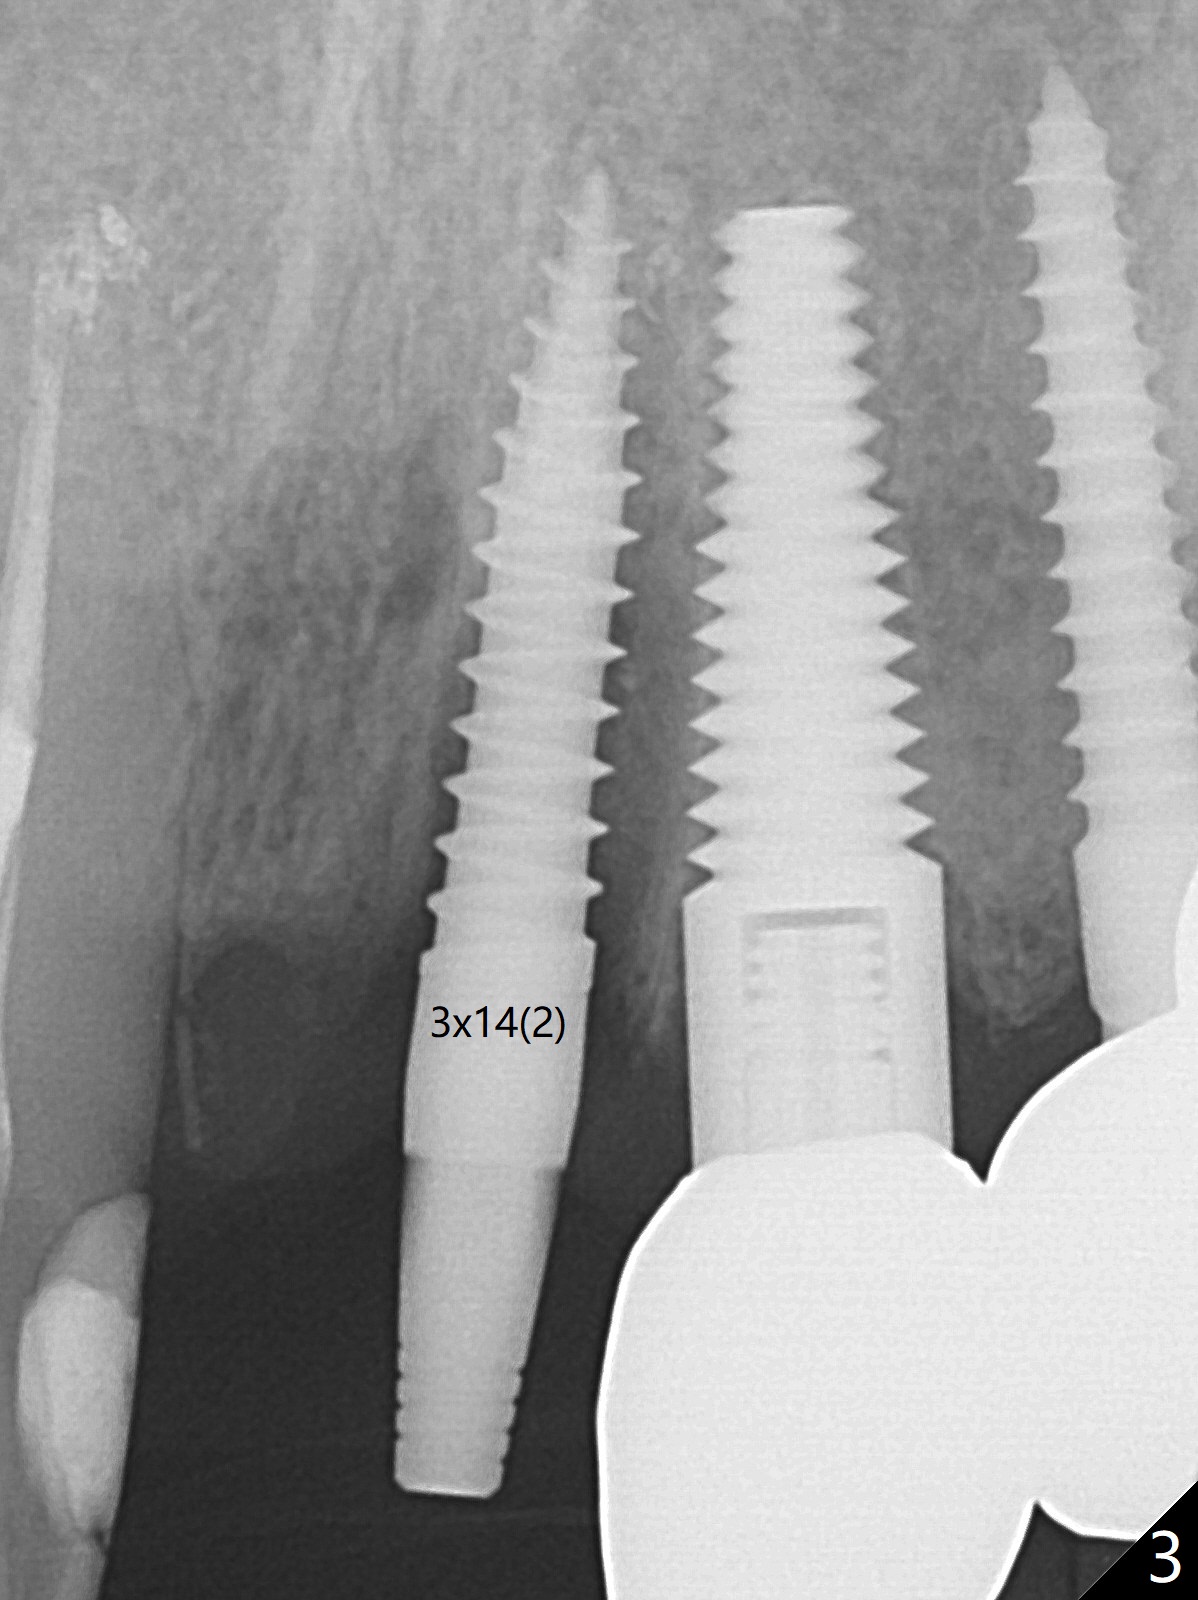

徒手种植不准确,需要反复调整,例如,为了避免接近侧切牙植体,中切牙钻洞开始于牙槽窝腭侧骨壁近中,结果接近切牙管(图一:红虚线),然后使用Lindamann bur移动钻洞,结果又太接近侧切牙(图二)。最后使用2毫米钻头试图改变钻洞方向,结果基台太接近侧切牙牙冠(图三)。而导板植入快,利索。 植入皮质骨骨粉(图四:*)后,制作临时牙冠。大约术后11天临时牙冠脱落(可能基台太短),病人没有及时复位,4天后牙槽窝愈合,可能变小,牙冠就位有些困难,造成颊侧牙龈发白(图五)。一周后牙冠又脱落,衬里后(图六:*)颊侧牙龈又显得饱满。